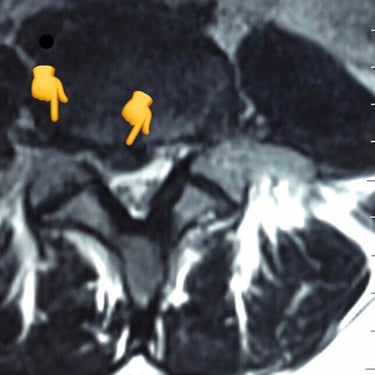

An intriguing case involved severe herniation and disc rupture between L4 and L5 vertebrae, causing intense pain. Opting out of surgery, the patient chose to try Discogel. Due to severe foraminal stenosis from the extruded disc, the Discogel injection was cautiously prolonged to one hour. Post-injection CT scan revealed effective penetration into fragmented disc components in the narrowed foraminal space.

The patient's pain gradually diminished after 4-5 weeks, and complete relief was achieved after several months.

The first image is six months post-injection, and the second image is three years post-injection."

Important Note: Foraminal disc herniation and migration into the intervertebral foramen significantly reduce the likelihood of a favorable response to Discogel injection and are not recommended for such cases.